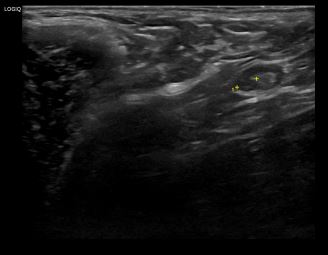

상기환자는 외부검사 이상소견으로 내원하신 60대초반 여성분으로 의심스러운 좌측 혹 조직검사 시행해 유방암 진단되었습니다